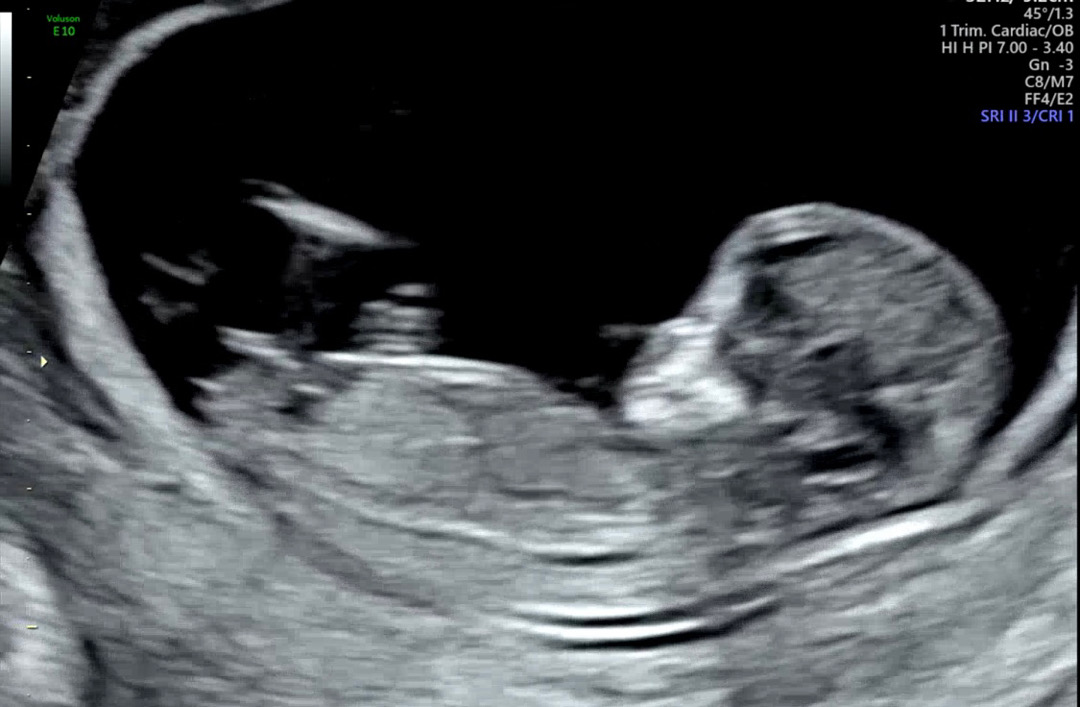

성별 봐주세요ㅠㅠ!!!!!

넘 궁금해요ㅠㅠ

딸같아요!